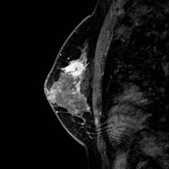

画像中偏上处白色不则部分为癌(治疗前)

治疗6个月后,白色部分变小

治疗一年后白色部分有明显缩小的变化